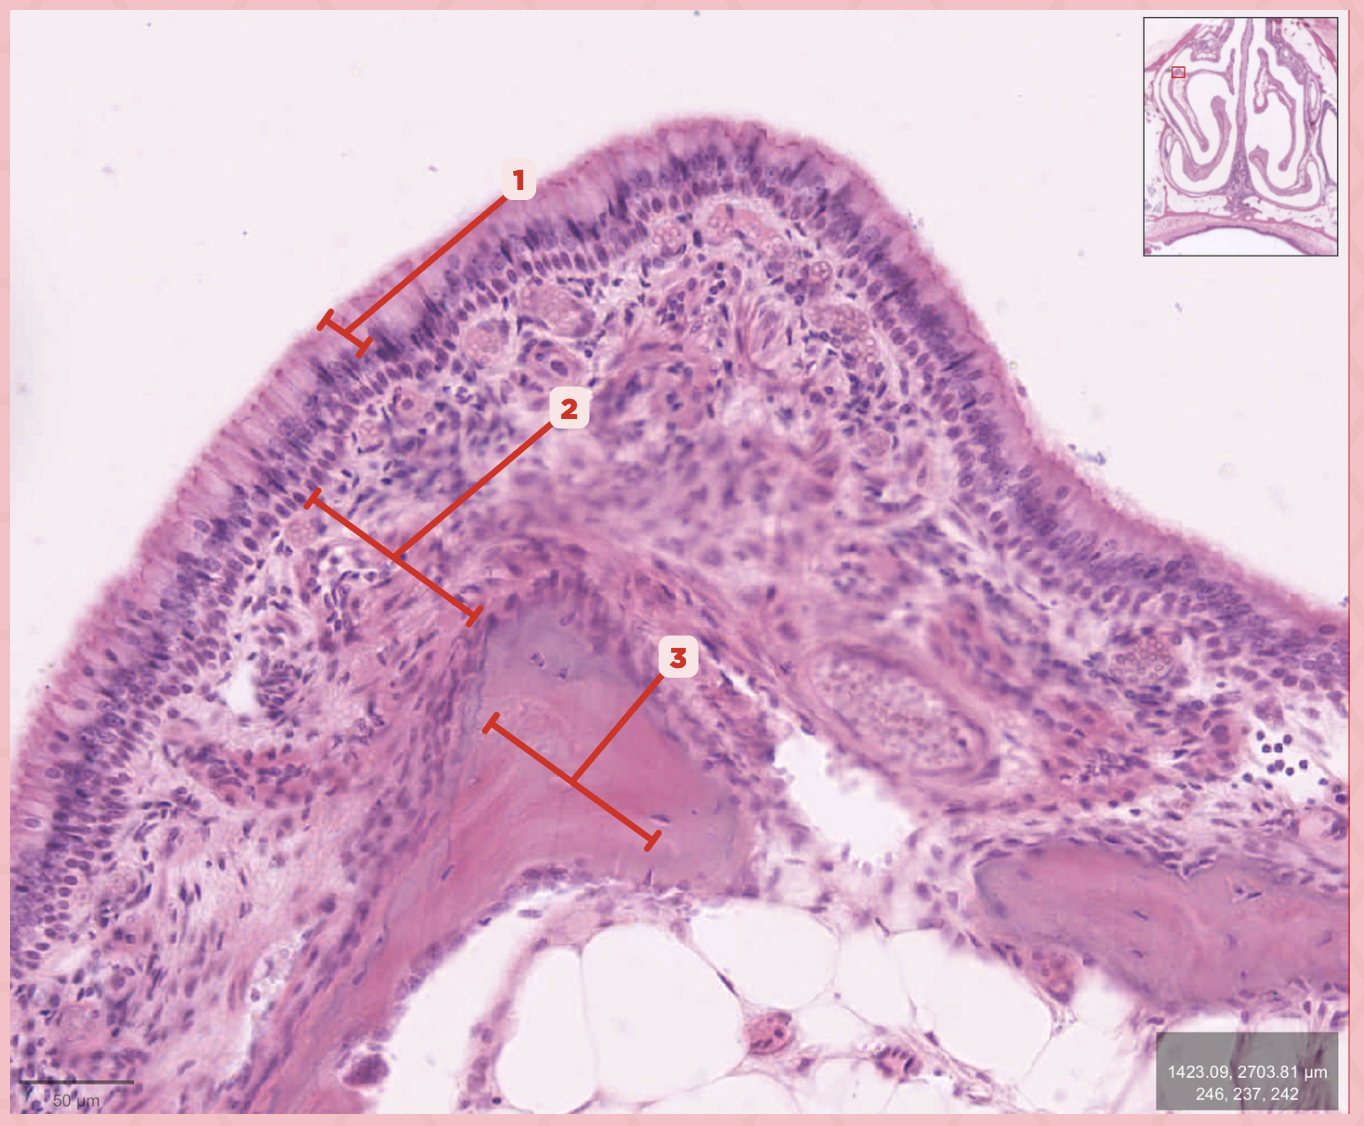

Respiratory Epithelium

Identify the structure labeled as 1.

Lamina Propria

Identify the structure labeled as 2.

Bony spicule

Identify the structure labeled as 3.

Respiratory Epithelium

What epithelium lines this structure?

Ciliated pseudostratified epithelium

What type of epithelium lines this structure?

Respiratory Epithelium

Identify the structure labeled as 1.

Mucosa

Identify the structure labeled as 2.

Bone

Identify the structure labeled as 3.

Keratinized stratified squamous epithelium

What’s the lining epithelium at #3?

No

Are Glands present at #1?

Lamina Propria

Identify the structure labeled as 1.

Adipocytes

Identify the structure labeled as 2.

Keratinized stratified squamous epithelium

Identify the structure labeled as 3.